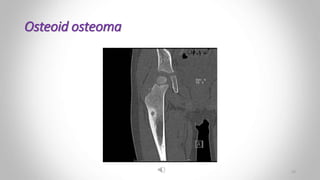

Osteoid osteoma :

• Is a painful condition

• Most commonly in the femur and tibia

• Young adults.

• A small lucency

• Sometimes with central specks of calcifcation, known as a ‘nidus’, surrounded by a dense sclerotic rim.

• Periosteal reaction may also be present .

• Radionuclide bone scanning, which shows marked focal increased activity.

• Radionuclide bone scanning is particularly useful when the osteoid osteoma is:

• Difficult to see on plain film

• And is helpful in locating the tumor during surgery

 Osteoid osteoma :

(a) Plain flm showing an area of sclerosis at the upper end of the tibia (arrows)

(b) CT scan showing sclerosis with a central lucency known as a nidus (arrow).

Osteoid osteoma